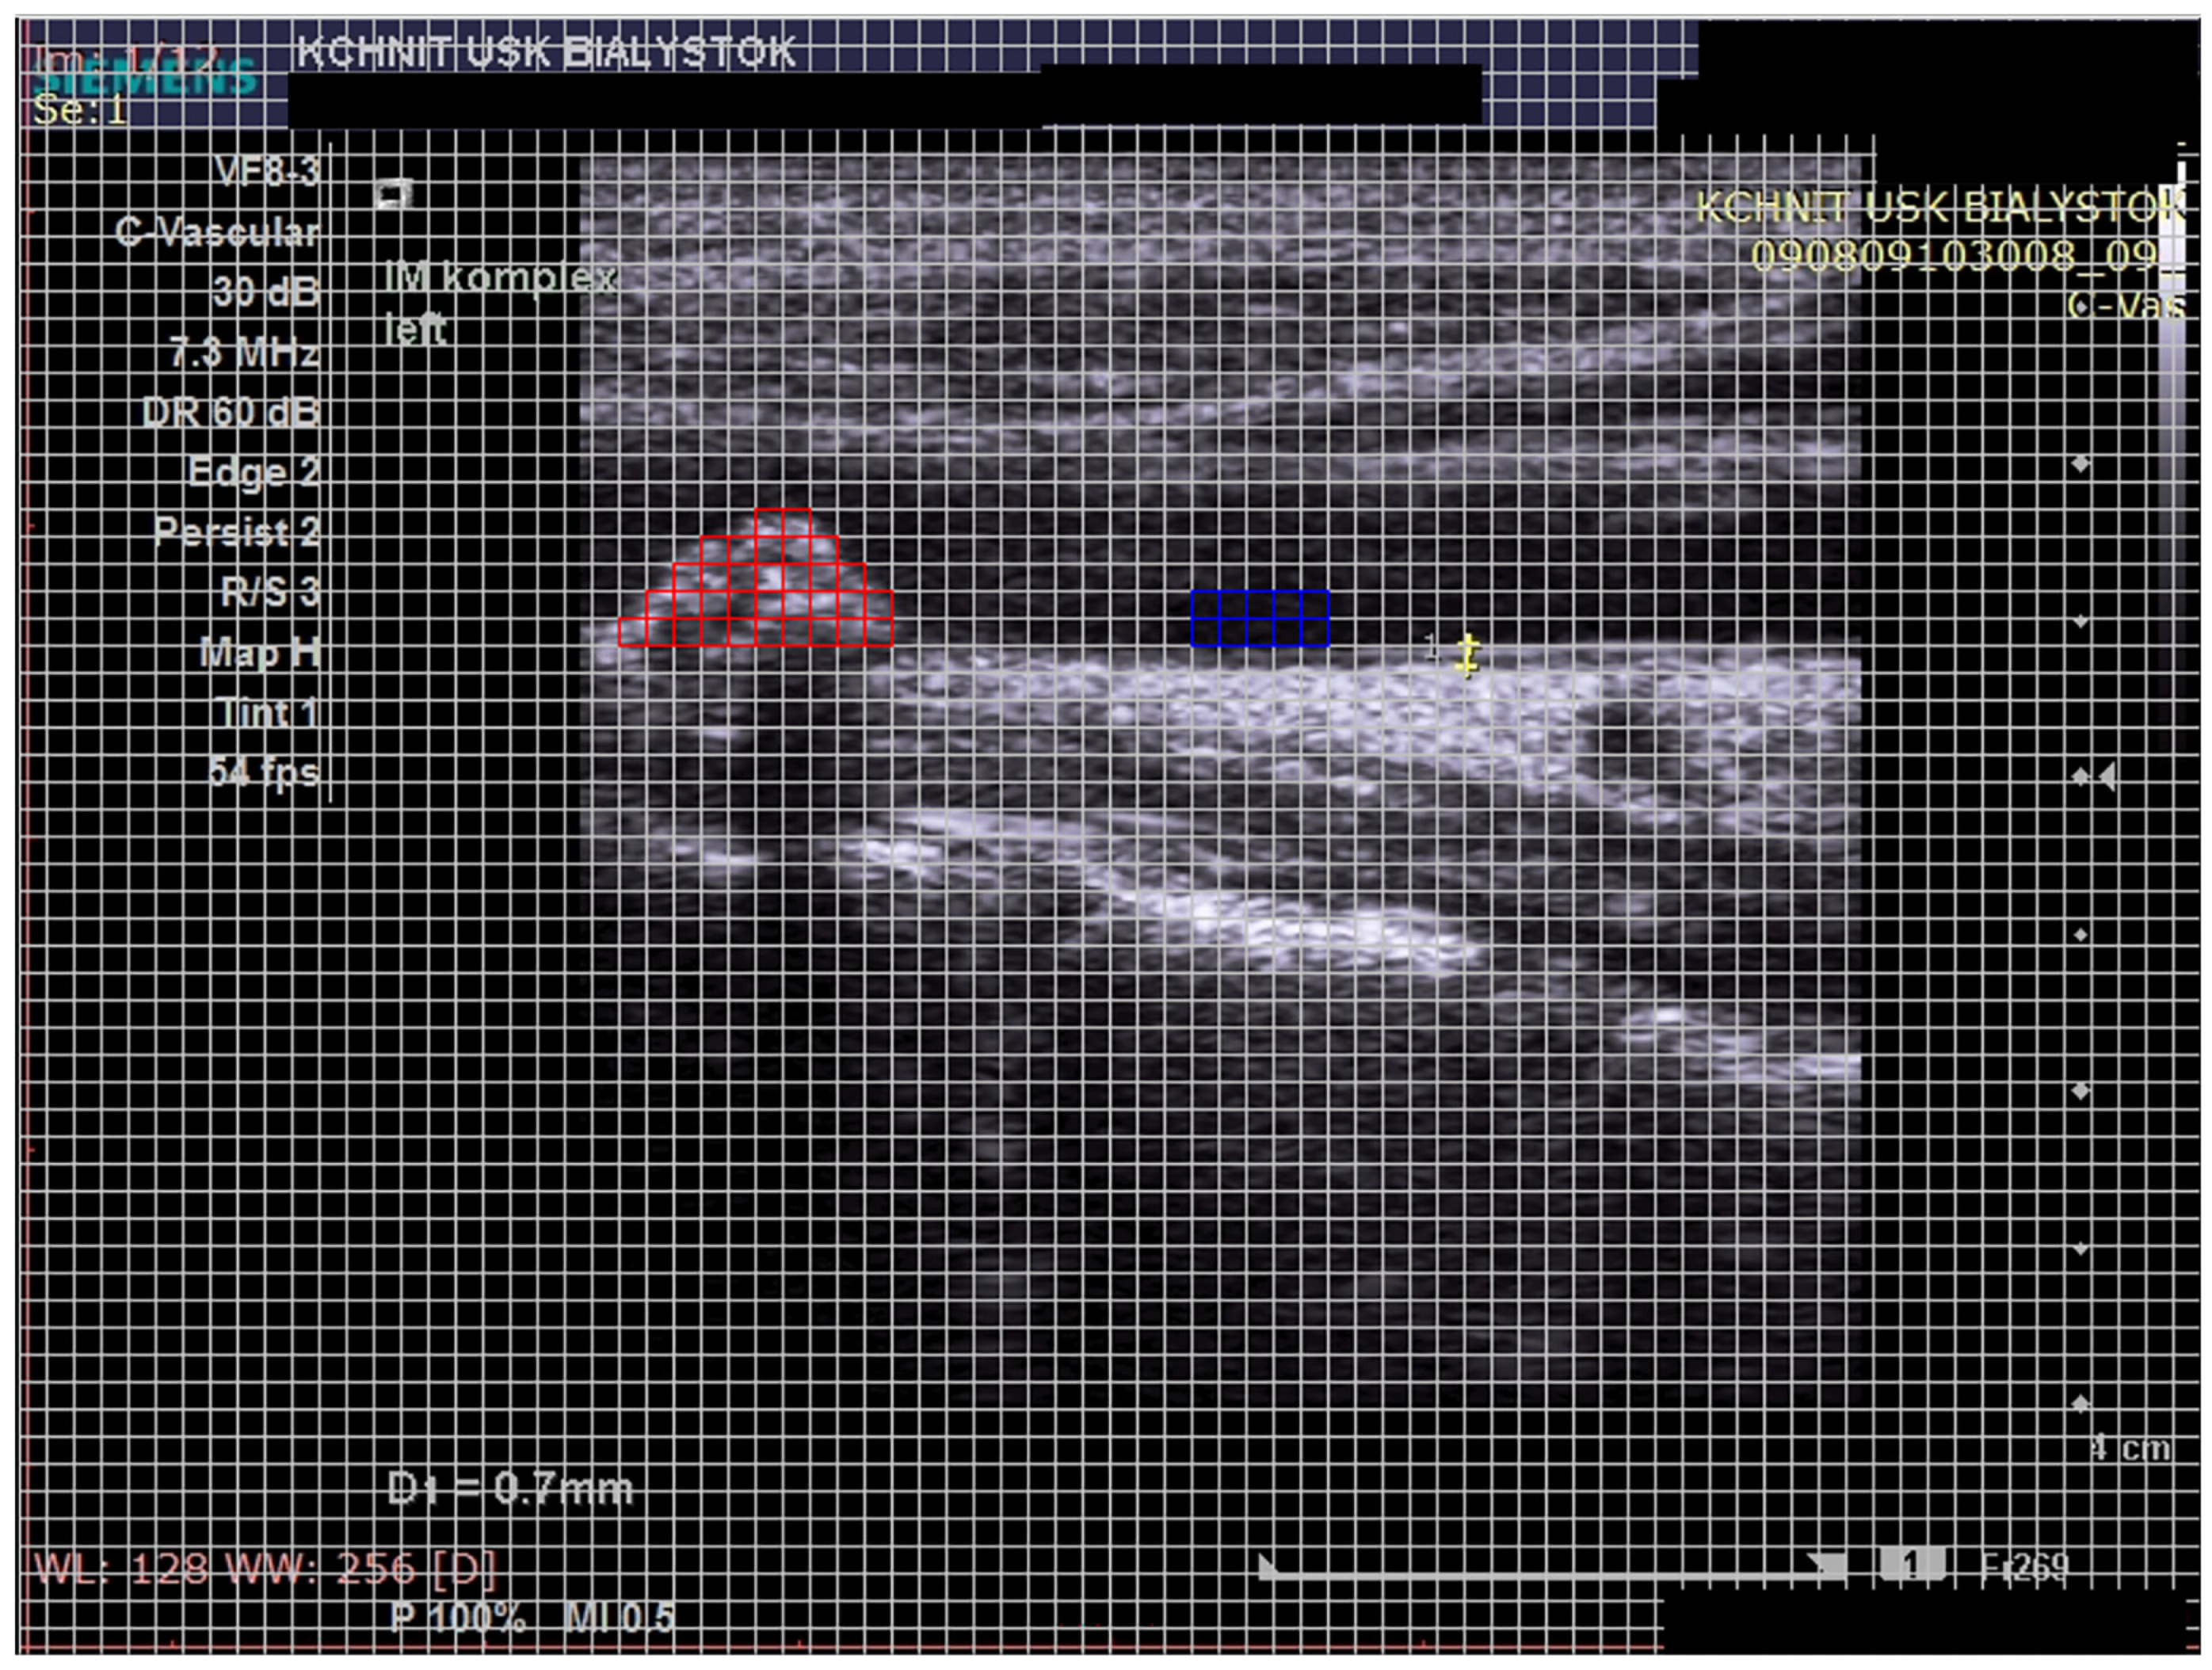

- Atherosclerotic plaque—during the ultrasound examination, the best possible image projection in B-mode presentation was selected with the entire atherosclerotic plaque visible—the image was not enlarged or brightened—according to the accepted standardization. The image of the plaque was recorded on a photograph. Then, to assess the atherosclerotic plaque, images from the ultrasound examination were used to analyze its structure on the GSM scale.

- Images of the visible atherosclerotic plaque in the carotid artery.

2.3.2. Image Standardization

2.3.3. Calculation of the GSM Value of Atherosclerotic Plaques